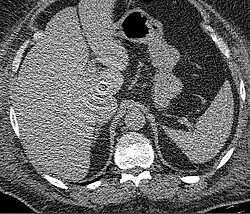

The acquisition of dual-energy data proves useful in clinical applications such as detecting uric acid versus calcium kidney stones, characterizing pulmonary embolism with iodine maps, and improving lesion conspicuity in liver imaging through virtual non-contrast and material decomposition.

.jpg)